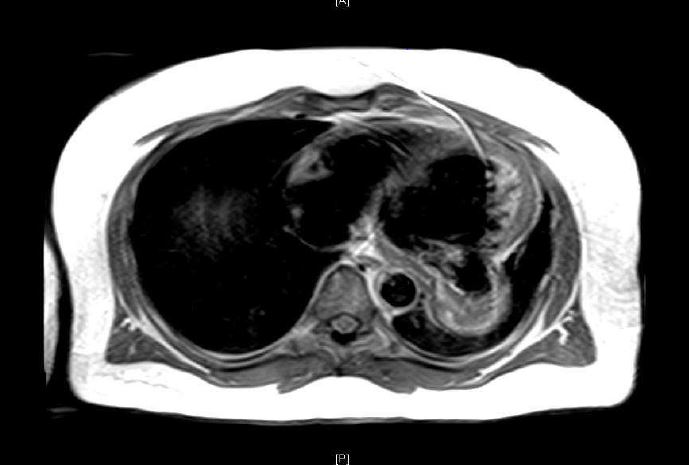

Case Presentation: A 44-year-old man with no known medical conditions presented with acute, painless, left monocular blurred vision. There was no history of smoking or illicit drug use. Physical examination indicated blood pressure of 200/135 mmHg, heart rate 86/min and unremarkable cardiopulmonary exam. Fundoscopic examination showed branched retinal vein occlusion. Patient had elevated Troponin I. Electrocardiogram had pathologic Q-waves in inferolateral leads. Chest X-ray displayed a retro cardiac opacity. Patient was initially managed for hypertensive emergency. Transthoracic echocardiogram (TTE) showed an ejection fraction of 25-30% with dyskinesis and outpouching of basal inferolateral wall concerning for possible pseudoaneurysm with thrombus. A subsequent transesophageal echocardiogram (TEE) confirmed a LV inferolateral PSA with chronic thrombus. Cardiac MRI was remarkable for a 4.6-cm x 6 cm x 5.6 cm PSA with a 3 cm neck and chronic thrombus. Coronary angiography with left ventriculogram showed two-vessel disease (60% proximal LAD and 100% distal RCA) with collaterals and LV outpouching equivocal for pseudo vs true aneurysm. Neck of the aneurysm was not visualized.

Discussion: Free wall rupture of the left ventricle (LV) contained by the adhering pericardium, results in formation of a LV pseudoaneurysm (PSA). A true LV aneurysm, in contrast, is the discrete thinning (<5mm) and resultant outpouching of the ventricular wall. Natural course for pseudoaneurysm is to rupture leading to cardiac tamponade, shock, and death. True aneurysm usually has a benign history, therefore PSA warrants an emergent surgery as compared to an elective surgical repair of aneurysm. Differentiating the two conditions preoperatively, despite the use of various cardiac imaging modalities, remains a challenge to date. We present a case report demonstrating these diagnostic difficulties.

Conclusions: The distinction between true and pseudo LV aneurysm is diagnostically challenging. Both types of aneurysms present with nonspecific symptoms and are mostly incidentally noted on cardiac imaging. When identified, it is important to distinguish accurately between a PSA and true aneurysm given the differing natural history and therapeutic strategies. Echocardiography, left ventriculography and contrast-enhanced cardiac MRI all provide useful information but are not definitive for preoperative diagnosis. Imaging characteristics most suggestive of PSA included a sharp discontinuity of the endocardial border at the base of the pseudoaneurysm, a narrow orifice compared with the aneurysm fundus diameter (Omax/Dmax 0.5 or less) and loss of epicardial fat with blood flow turbulence. Surgical exploration and pathologic assessment is necessary to make a definitive diagnosis.